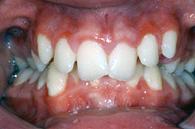

| Tiefbiss | Kreuzbiss vorne | |